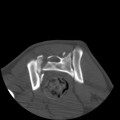

CT - lebka